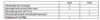

Du er forvagt på urologisk afdeling og godkender prøvesvar på denne patient. Patienten har været set af din kollega i akutmodtagelsen for 3 dage side med nyrestensanfald. Du kan læse i patientens journal, at patienten på daværende tidspunkt havde flankesmerter på venstre side. Der er bestilt en undersøgelse mhp. at vurdere nyrernes funktion og afløbsforhold. Den er foretaget i dag og du ser her svaret mhp. godkendelse. (LT=venstre, RT=højre)

Hvad hedder undersøgelsen?

renografi

Hvad viser undersøgelsen? (Vælg det rigtige svar)

- Normalt afløb fra begge nyre.

- Normalt afløb fra højre nyre, mistanke om nedsat afløb fra venstre nyre

- Normalt afløb fra højre nyre, intet afløb fra venstre nyre

- Normalt afløb fra venstre nyre, mistanke om betydende afløbshindring fra hø nyre

- Normalt afløb fra højre nyre, intet afløb fra venstre nyre

Note: svaret til spørgsmålet er forskelligt i forskellige sæt.

Bedste bud: “mistanke om nedsat afløb”